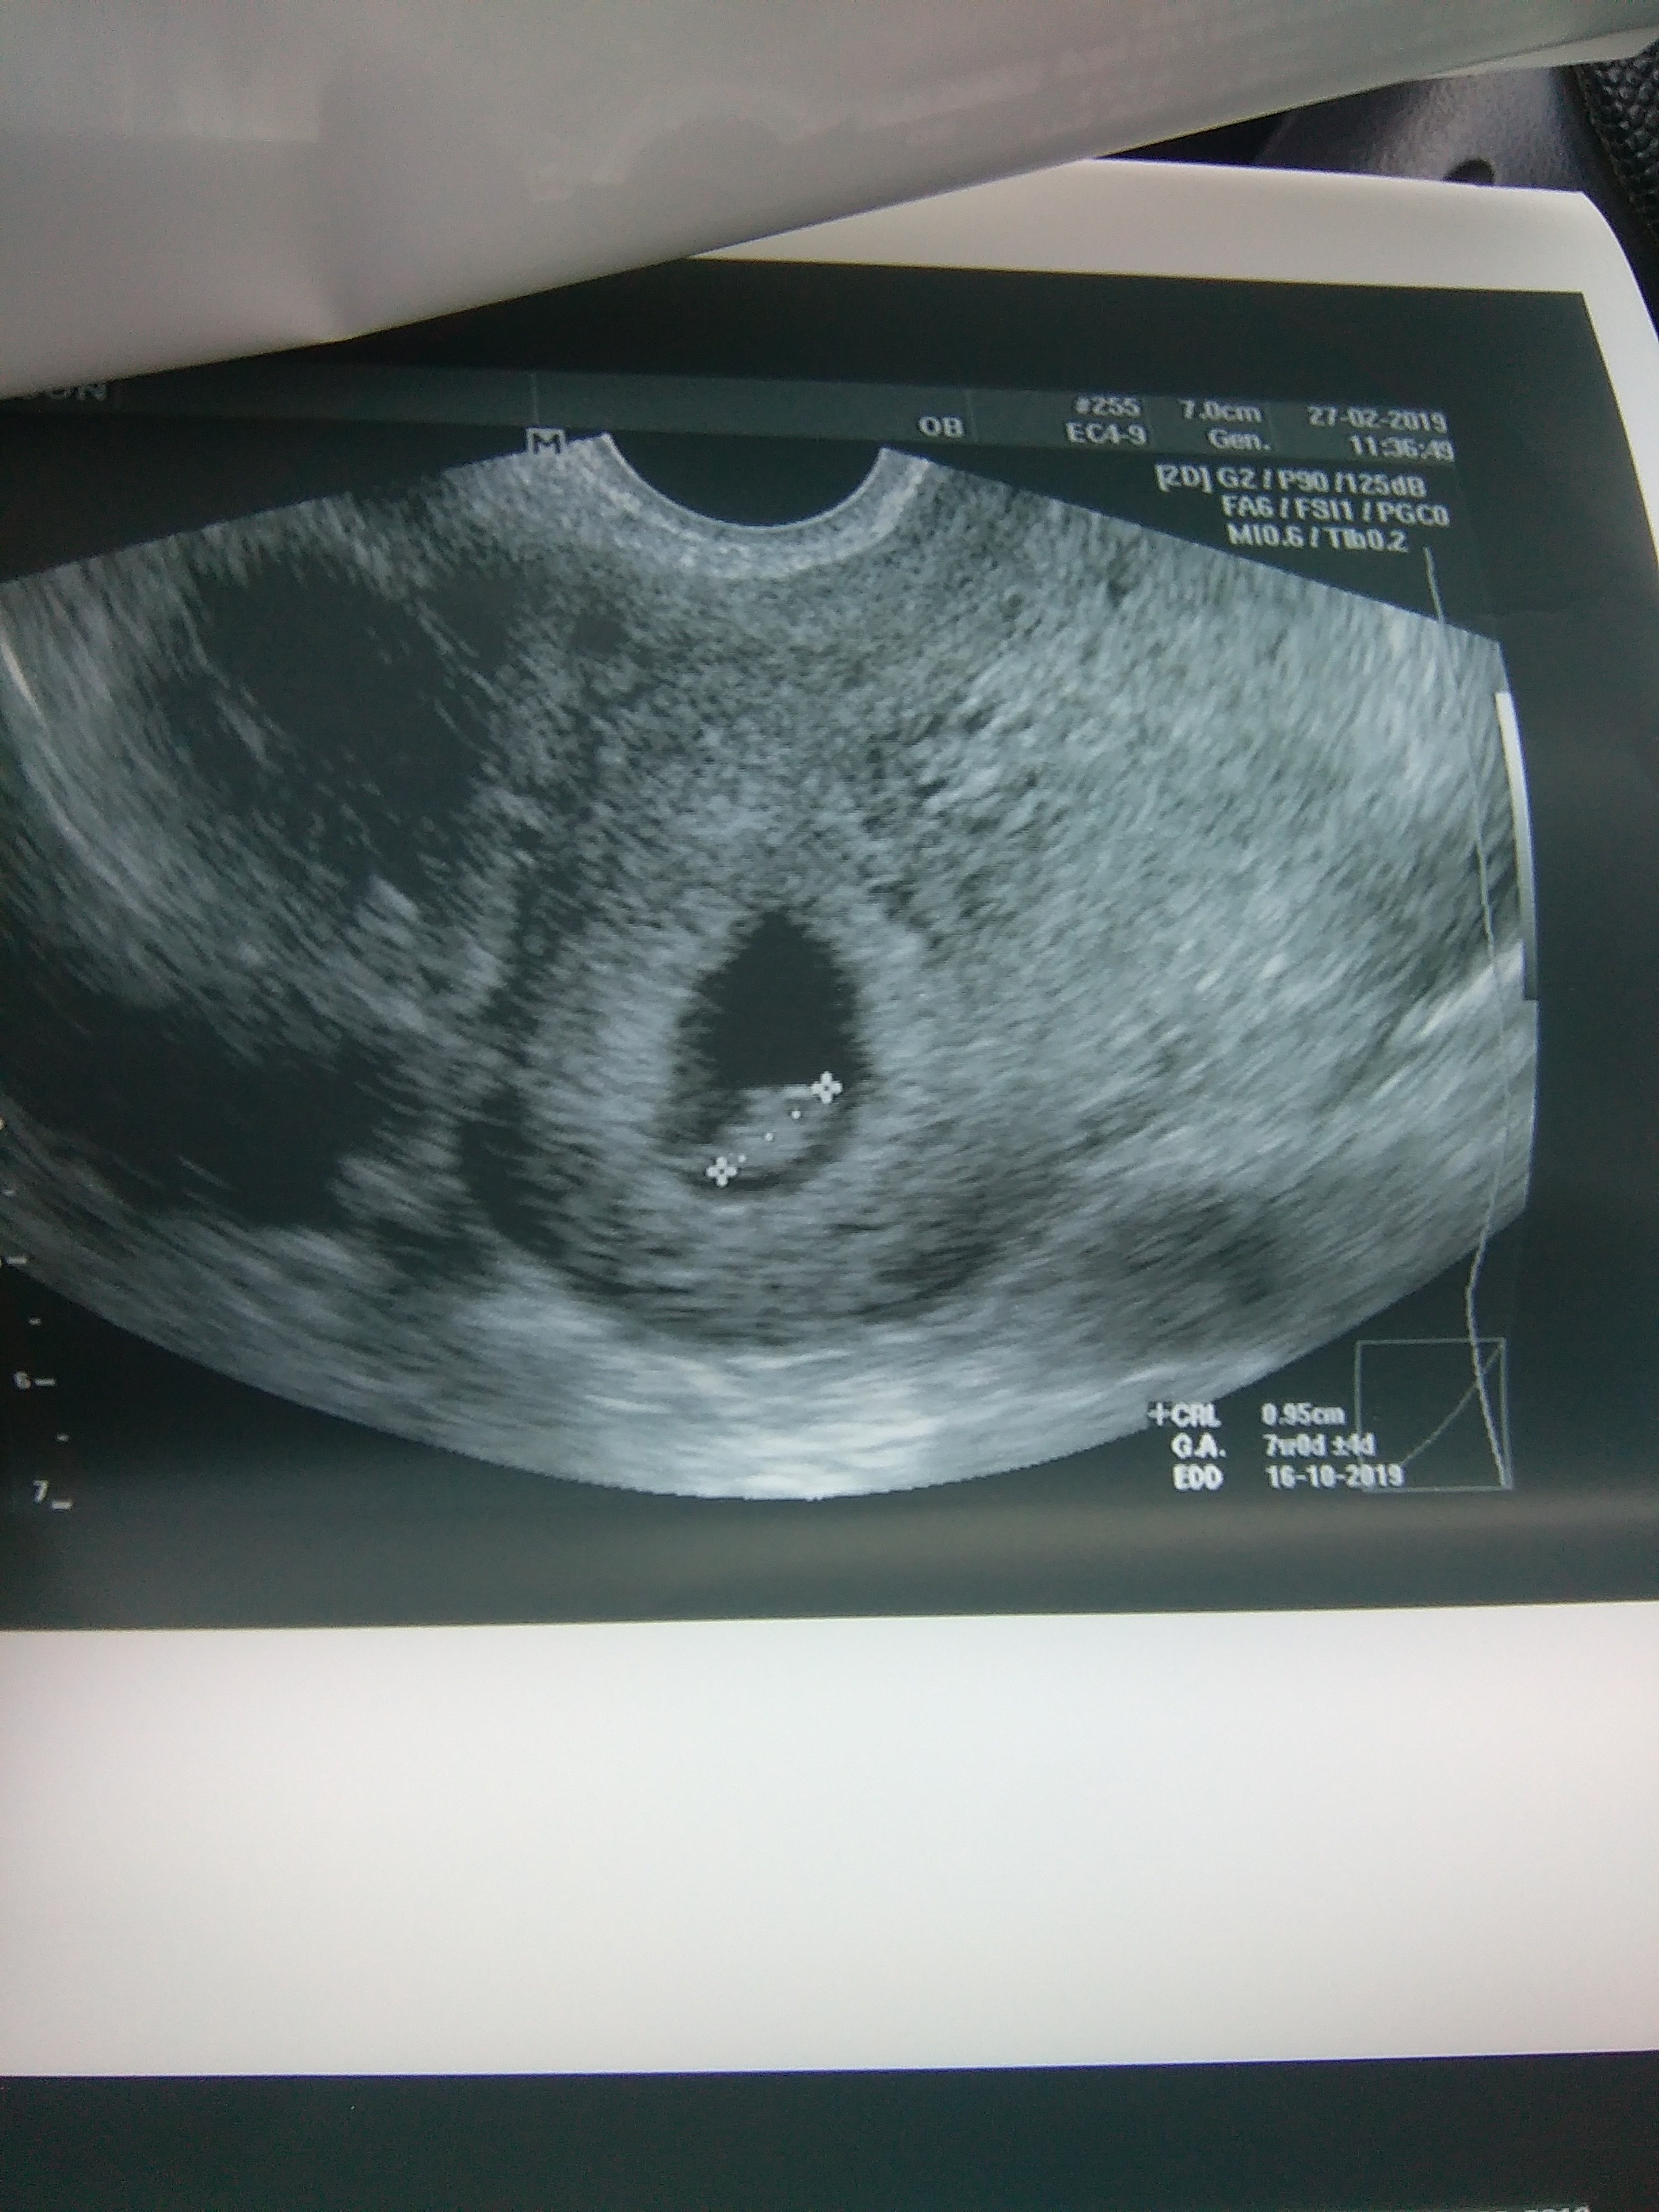

7+0

Witam się po wizycie ;) i przedstawiam kropka wielkiego :) 0,95 cm z bijacym serduszkiem :)

IMAG3004.jpg